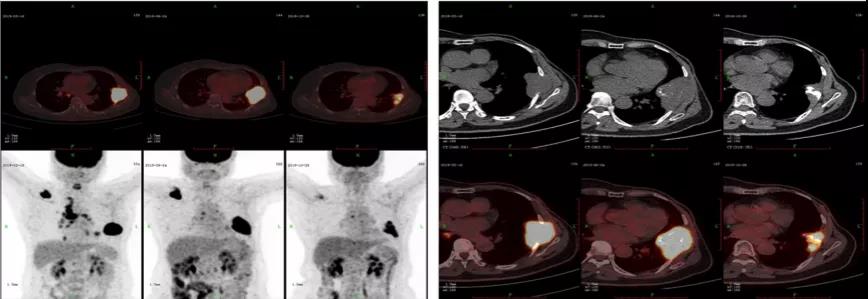

治疗接近3个月的复查:2019.6.24 PET-CT首次复查评估,考虑右侧颈部、纵膈、双肺门、右肺下叶转移灶退缩,SUV值下降。右侧肩胛骨转移、左侧胸壁转移伴有肋骨病理性骨折病灶变大,SUV值下降(胸壁肿物7.7*4.6cm,SUV12.4)(原胸壁肿物5.8*4.5cm,SUV17.2)。

患者治疗后全身其余病灶退缩良好,胸壁转移的肿物体表退缩明显,但是向内部增大,鉴于Ki67数值极低,肿瘤增殖活性明显受到抑制,肿瘤影像学增大与增殖活性受抑制有不一致的地方,无法给予明确的肿瘤进展结论。与患者沟通后在密切观察基础上审慎继续使用哌柏西利+AI治疗,此后密切定期CT平扫,胸壁肿物逐渐缩小。2019.4肿物5.8*4.5cm;2019.6肿物7.7*4.6cm;2019.7肿物5.2*3.5cm;2019.9肿物4.3*2.8cm。

2019.10.28 PET-CT复查评估,右侧颈部、纵膈、双肺门、右肺下叶转移灶基本都退缩,SUV值接近正常。右侧肩胛骨转移、左侧胸壁转移伴有肋骨病理性骨折病灶变小,SUV值下降(胸壁肿物3.9*2.5cm,SUV3.1)。